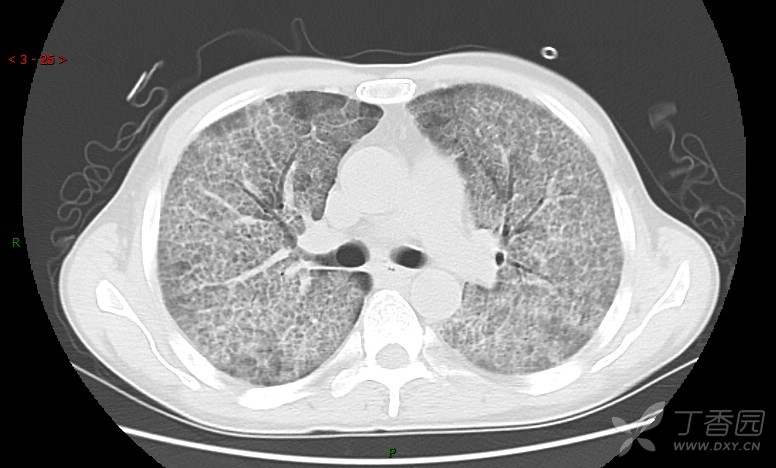

地图+铺路石征=PAP?那升高的CEA怎么说(病例3连发,附其他2例链接)

患者男,42岁,咳嗽半年余,加重伴憋喘2月余。

患者半年余前无明显诱因出现间断咳嗽,干咳为主,偶咳少量黄白痰,剧烈咳嗽或运动后可出现轻度憋喘,无高热、脓臭痰,无胸痛、咯血及晕厥,无低热乏力及盗汗,无心前区压榨感及夜间阵发性呼吸困难,初未在意,未予正规诊治。2月余前患者自觉上述症状较前加重,咳嗽、憋喘明显,黄白色粘痰略有增多,伴有发热,热前伴有畏寒、寒战,体温最高达38.9℃,先后就诊多家医院,入住重症监护室,未行气管插管,考虑“重症肺炎”,给予“美罗培南、复方磺胺甲噁唑”等药物抗感染,“卡泊芬净”抗真菌,并给予“甲泼尼龙”等药物治疗35天,经治疗后症状好转于2018-04-02出院。患者自出院后仅应用中药治疗(具体不详),并给予家庭氧疗,平素仍有间断咳嗽,咳少量黄白色粘痰,活动后憋喘明显,活动耐量差,以卧床为主。

血清肿瘤相关抗原116.22U/ml↑(0--95);

癌胚抗原 61.96 ng/mL ↑ 0--5

神经特异性烯醇化酶 33.12 ng/ml ↑ 0--16.3

细胞角蛋白19片段测定 40.23 ng/ml ↑ ≤3.3

肺内弥漫性网状结节影,PET-CT却无阳性病灶,这是?(附其他2例链接)